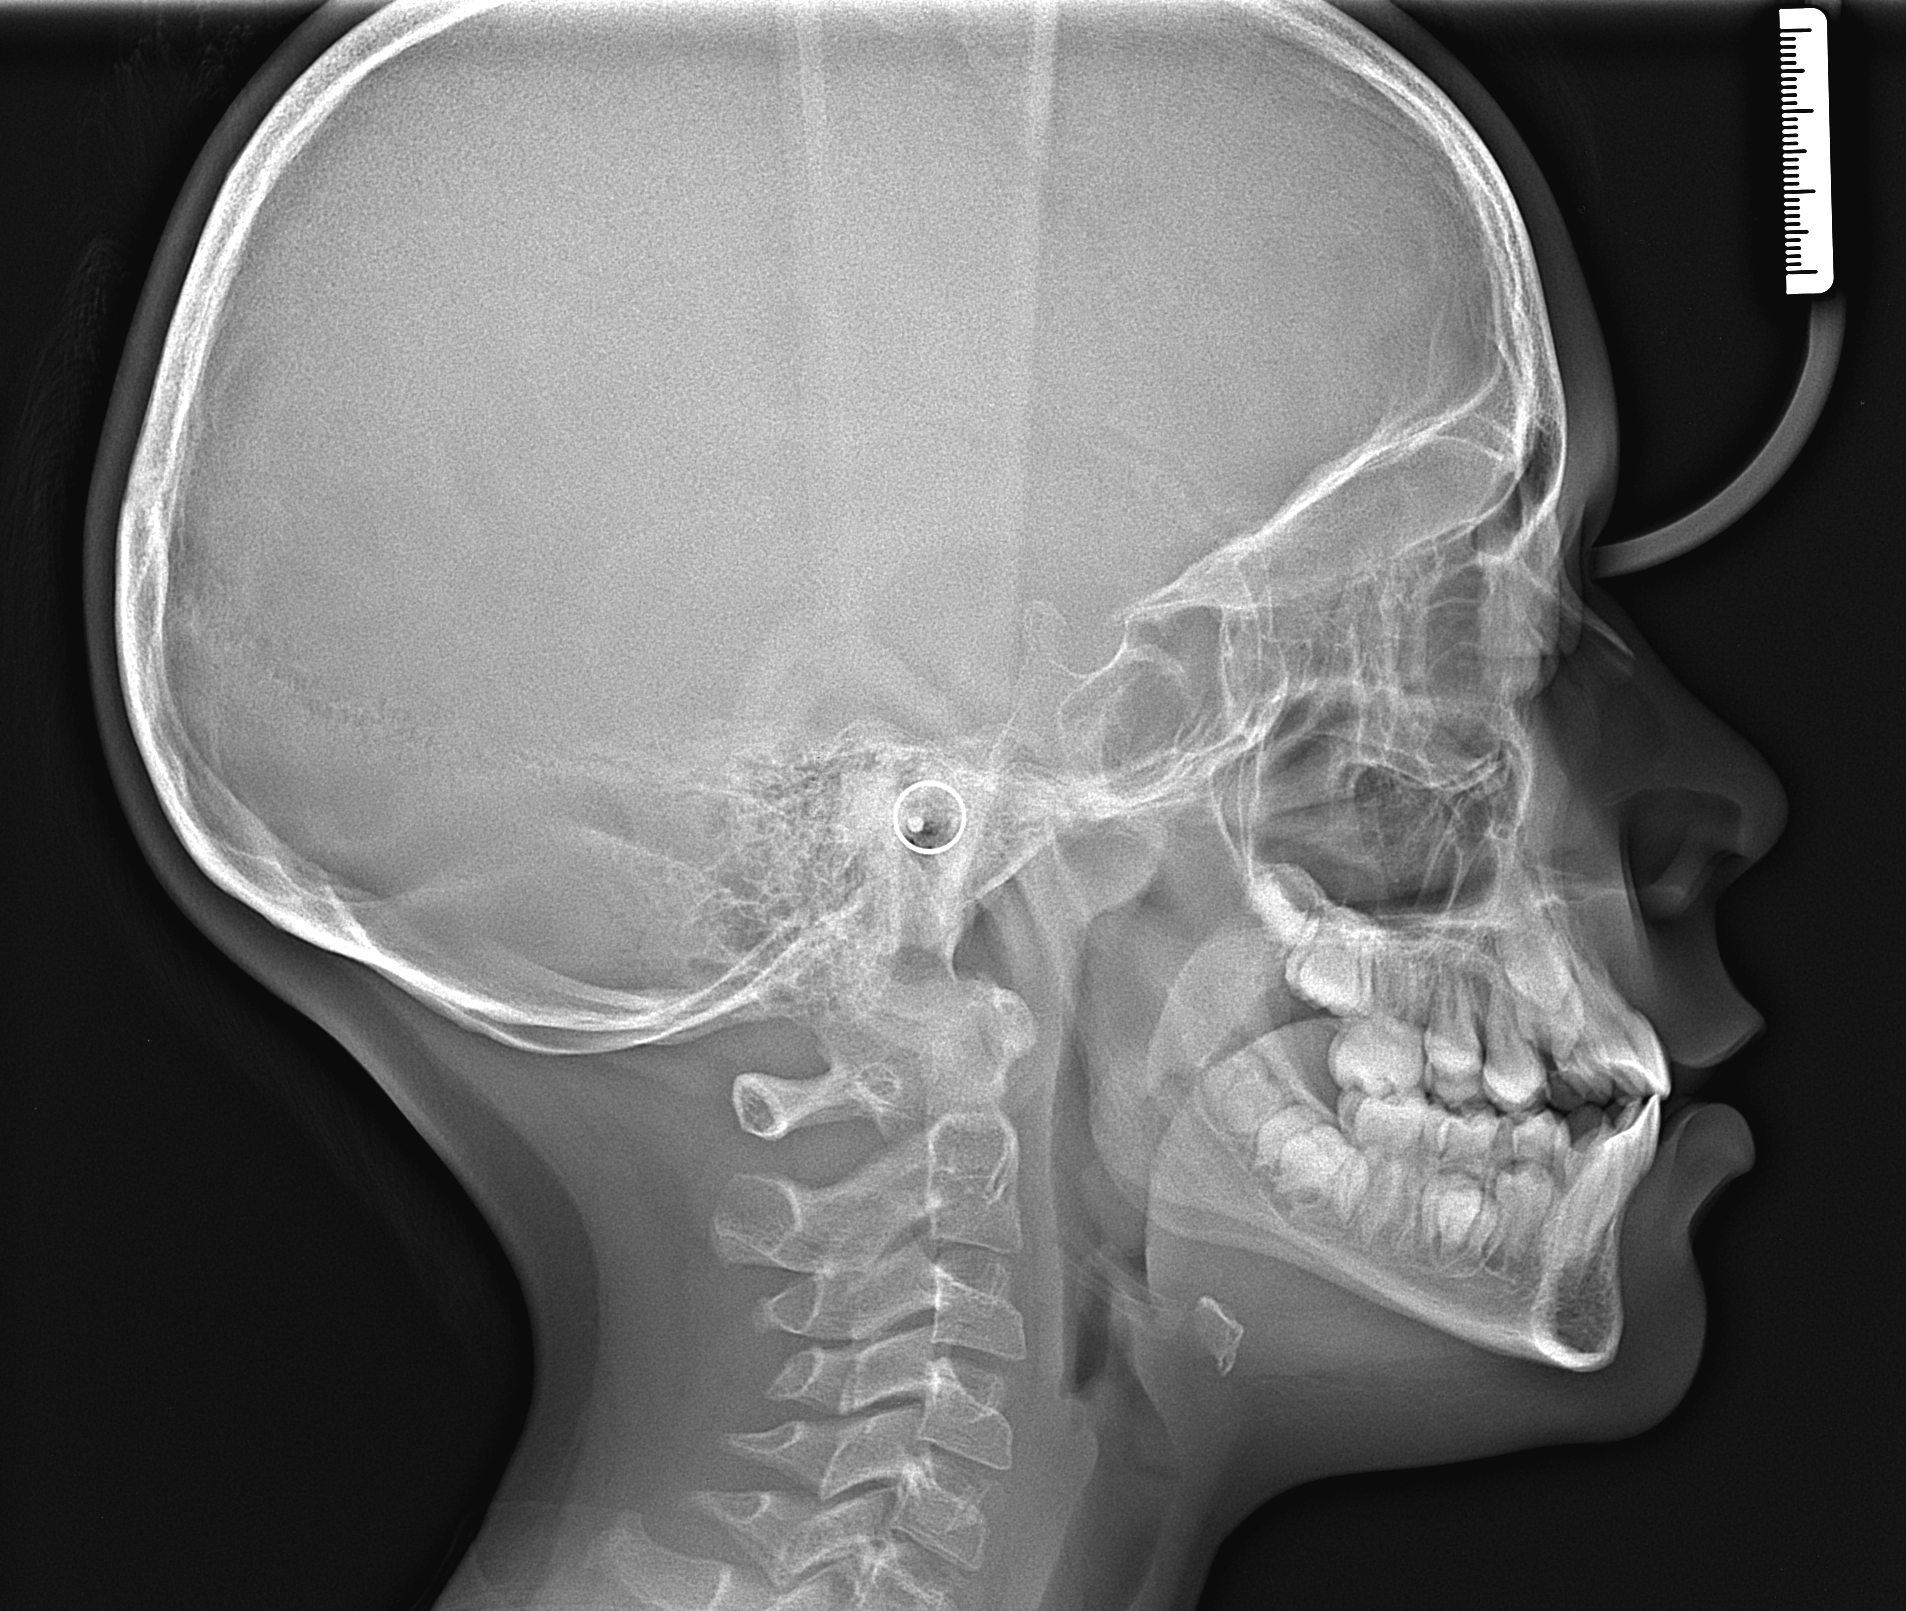

Фотографии и схемы для ОПТГ и мезиального прикуса